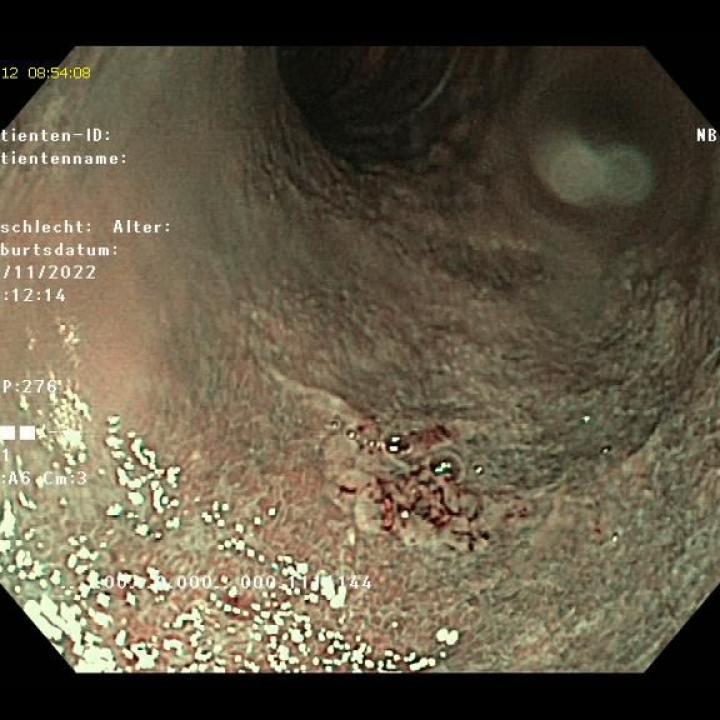

Die Gastroskopie (Spiegelung des Magens) ist ein medizinisches Untersuchungs- und Therapieverfahren. Dabei wird ein Endoskop über Mund oder Nase eingeführt und durch die Speiseröhre in den Magen vorgeschoben. Die korrekte Bezeichnung dieser Methode ist heute Ösophagogastroduodenoskopie (ÖGD). Mit ihrer Hilfe ist es möglich, das Innere der Speiseröhre (Ösophagus), des Magens (Gaster) und des Zwölffingerdarms (Duodenum) anzusehen.

Für die Untersuchung werden flexible Gastroskope eingesetzt. Außer einigen wenigen Spezialanwendungen können alle Aufgaben mit den flexiblen Instrumenten schneller, bequemer und für den Patienten schonender erreicht werden. Flexible Gastroskope haben heute einen Durchmesser < 10mm und können damit auch bei sehr kleinen Tieren eingesetzt werden. Sie können tiefer eingeführt werden und haben eine geringere Verletzungsgefahr.